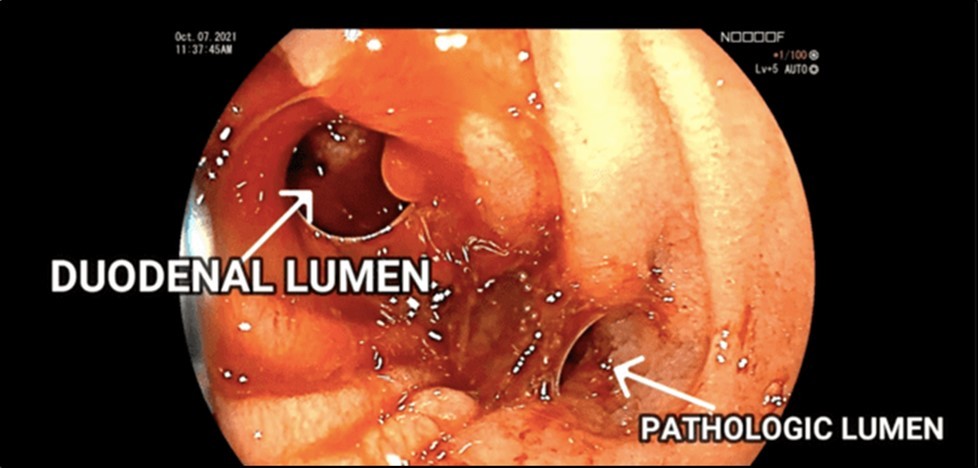

Esophagogastroduodenoscopy (EGD) revealed a fistulous opening in the third part of the duodenum and a bleeding vessel. (Figure 1) Bleeding was controlled with injection hemostasis and 3 hemoclips were deployed. The colonoscopy revealed a large obstructing, polypoid, ulcerating, and circumferential mass with areas of necrosis that was seen at the proximal transverse colon which precluded further advancement of the scope. Biopsy samples were sent for histopathology investigation and TB polymerase chain reaction (PCR) test.

Figure 1.EGD findings of a pathologic lumen and a bleeding vessel were seen at the third portion of the duodenum.